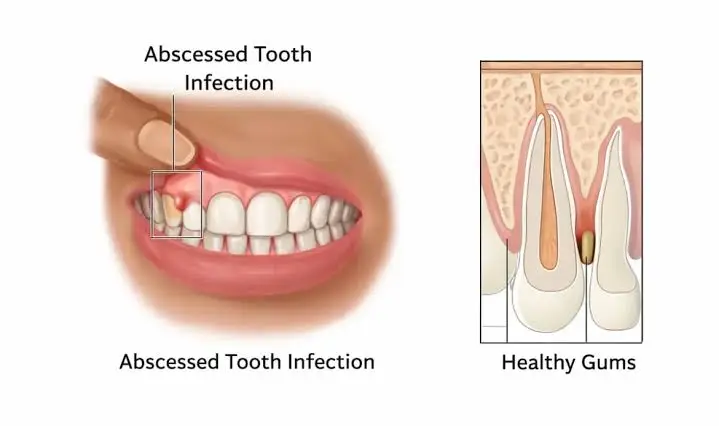

What Underestimated Signs Distinguish A Tooth Infection From Simple Sensitivity?

Many people dismiss persistent tooth pain as mere sensitivity, overlooking subtle but telling indicators of a deeper issue. You may notice prolonged discomfort after eating hot or cold foods, but when swelling appears, or a small pimple-like bump forms on your gum, the cause is likely bacterial invasion. Unlike transient sensitivity, infections can compromise overall […]